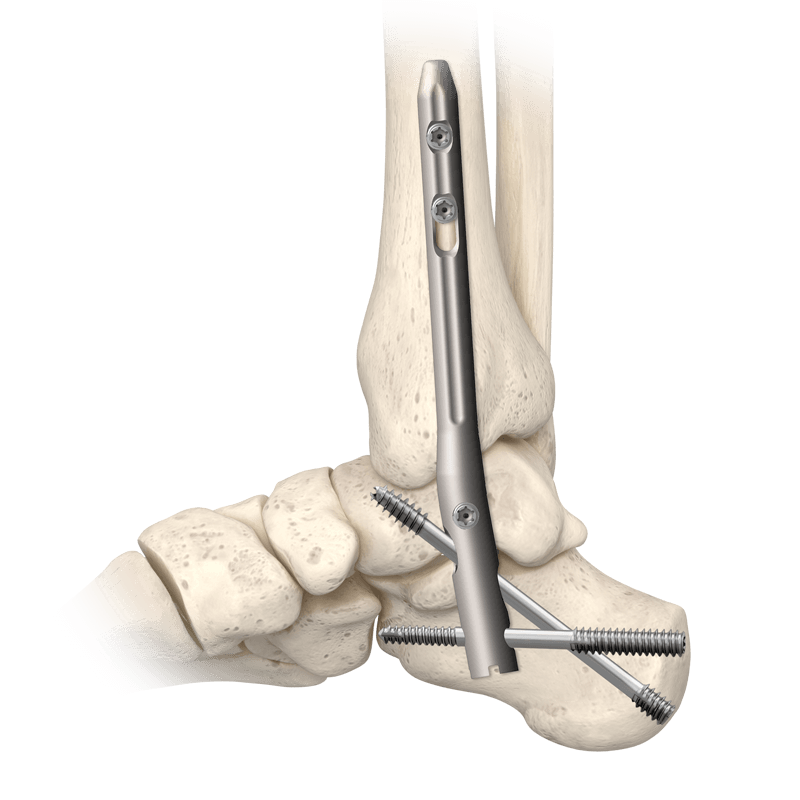

CoLink® NeoFuse Ankle Fusion Plating System

For anterior fixation of ankle arthrodesis and fractures